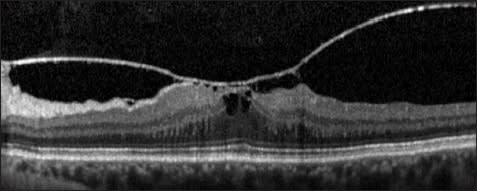

After vitrectomy, ultrahigh-resolution and SD-OCT have demonstrated outer foveal photoreceptor disruptions; a clear cystic space in the outer retinal layers of the fovea is often present (Figure 6). Over time, these disruptions get smaller, although often they do not disappear completely.38- 41 Similar outer retinal defects may be seen after spontaneous closure of macular holes.15,16,22 The size of disruptions of the IS/OS junction measured on SD-OCT is correlated with visual acuity after macular hole repair.12-14

Figure 6. Full-thickness macular hole. The top is a picture of a stage 2 macular hole. Persistent vitreofoveal traction is apparent. On the bottom is an OCT image of the same patient three months after surgical repair. Note a small cystic space in the outer layers of the fovea. The fovea is enlarged, and the outer retinal layers are labeled: ELM (external limiting membrane); IS/OS (photoreceptor inner/outer segment junction); and PROS (photoreceptor outer segments).